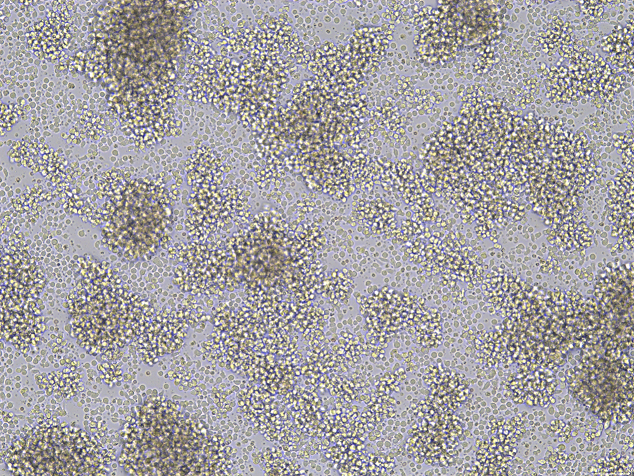

细胞特性:悬浮生长,数量多时聚集成团,数量较少则零散分布。CD2、CD7、CD11a、CD28、CD45、CD54表面标记为阳性;CD1、CD3、CD4、CD5、CD8、CD10、CD14、CD16、CD19、CD20、CD23、CD34、HLA-DR表面标记为阴性。

细胞图片:

(4)培养时注意观察成团大小,以松散透光团状最佳,若观察到细胞团过于紧密且中心呈灰黑色,可在补液时轻轻吹打2-3下。